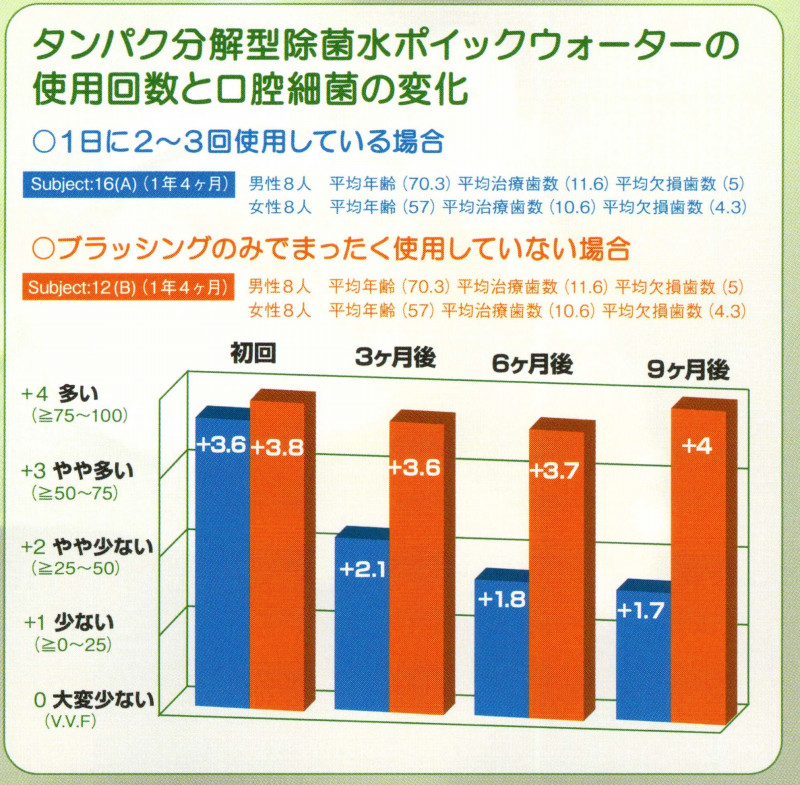

Q, POICウォーターを使用した殺菌治療症例

歯の表面に紫色に染めたプラークが付着していなければ、歯の表面が殺菌されていることになります

POICウォーターと正しいブラッシングをおこなうことができれば、誰でもご自宅で簡単に殺菌治療をおこなうことができるのが、歯科医院専売のPOICウォーターの効果です